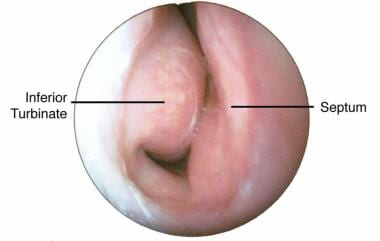

Projecting out of the lateral walls of the nasal cavity are curved shelves of bone. The flow of air from outside of the body to the lungs begins with the nose which is divided into the left and right nasal passages.

The lateral nasal wall consists of inferior and middle turbinates and occasionally a superior or supreme turbinate bone. The turbinates consist of three ridges of thin shell like bone known as the nasal conchae. The nasal passages are lined with a membrane composed primarily of one layer of flat closely packed cells called epithelial cells.

Internally the nasal septum divides the nasal cavity into a right and left side. They connect to your nasal passages in a complex network of air flow and drainage passages. One of the functions of the nose is to drain a variety.